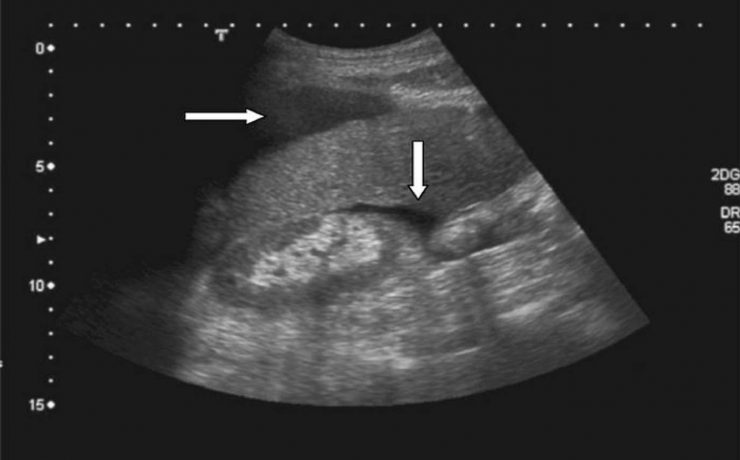

VESÍCULA DE PORCELANA

Es un término que se ha utilizado para describir la decoloración azulosa y la consistencia quebradiza de una vesícula biliar con calcificación extensa en su pared. Es una manifestación inusual de la colecistitis crónica, su máxima incidencia es la sexta década de la vida, tiene pocos síntomas generalmente dolor intermitente